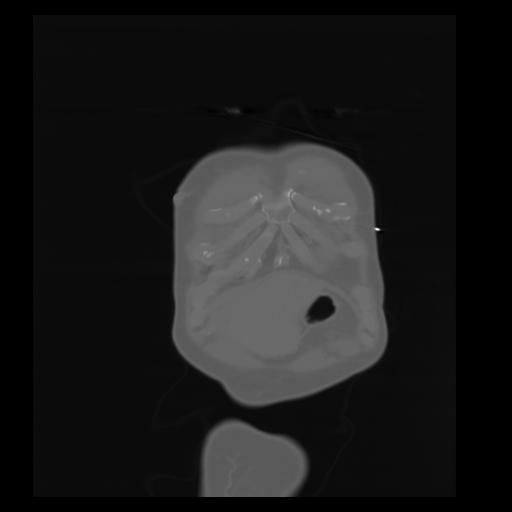

29 CUERPO,CE,Coronal,3.000,CUERPO,Coronal,